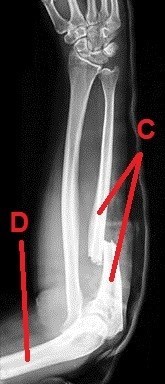

A dál co potřebujete k získání finálních souřadnic? Trocha z té zdravotnické praxe. Správný geokačer má silně vyvinutý smysl pro všímání si detailů, skrytých souvislostí a tak podobně. Princip je jednoduchý. Nepůjde o žádnou kdoví jak složitou matematickou šifru s IT podtextem. V budoucích několika minutách, hodinách či dnech se z Vás stanou radiologové (lékaři zabývající se zobrazovacími technikami) a anatomové. Tak Vás jistě nepřekvapí několik obrázků, na kterých bude vyznačen útvar, který musíte poznat a latinsky (pokud jiným jazykem, tak Vás na to upozorním) pojmenovat. Myslím, že vše bude jasné. Tak jdeme na to…

C - počet písmen v názvu zlomeného útvaru (latinsky, 1 slovo)

D - počet písmen v názvu útvaru (latinsky, 1 slovo)